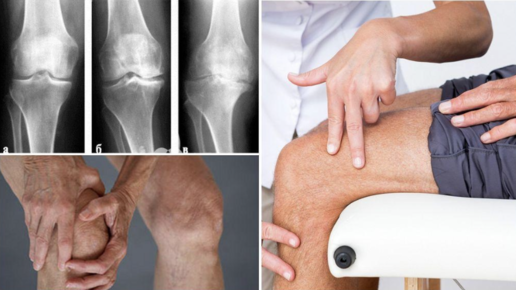

Боль, ломота, ноющие ощущения в суставах считаются неизменными спутниками старения. Однако в последние годы врачи-ортопеды, терапевты, неврологи все чаще слышат подобного рода жалобы и от довольно молодых пациентов. Такие симптомы могут быть признаком самых разных патологических состояний, среди которых лидирующее место занимает остеоартроз, также называемый деформирующим артрозом. Это заболевание проявляется дегенеративно-дистрофическими изменениями в суставных тканях, причем первым страдает хрящ...

Большинство людей с гонартрозом страдают от хронической боли. В начальной стадии она появляется лишь периодически, а на поздних стадиях становится постоянной и интенсивной. Обсудим, откуда берется боль при артрозе коленного сустава, какая боль бывает и как снимают боль. Виды боли при артрозе коленного сустава Боль – это основной симптом остеоартроза и главная причина обращения людей с этим заболеванием за медицинской помощью. Этот симптом развивается у всех без исключения больных, хотя он может возникать на разных стадиях...